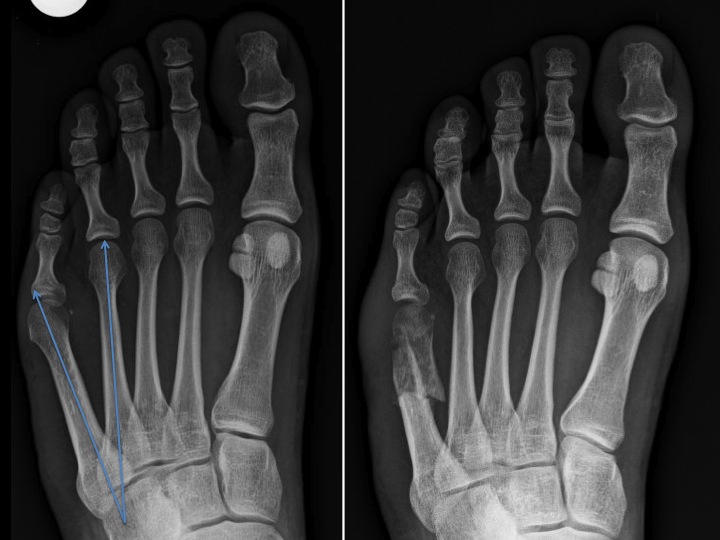

Type 1 : dans 33% des cas : augmentation de la taille de la tête du cinquième métatarsien situé sur le bord externe du pied : une réduction de volume sera recommandée.

Type 2 : dans 23% des cas : courbure latérale excessive du cinquième métatarsien ; une ostéotomie distale peut réajuster cette déformation.

Type 3 : dans 44% des cas : augmentation excessive de l’angle intermétatarsien 4-5 : une ostéotomie proximale ou une ostéotomie au niveau de la malformation permet de normaliser cet angle.